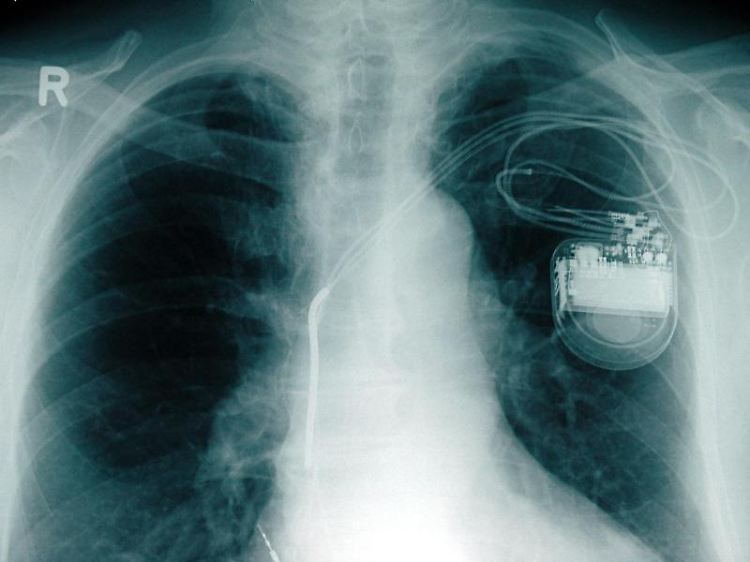

Brustkorb mit Herzschrittmacher: Im Jahr 2012 glaubten fast 12.500 Menschen in Deutschland, ihrem Arzt sei ein Behandlungsfehler unterlaufen.

(Foto: dpa)